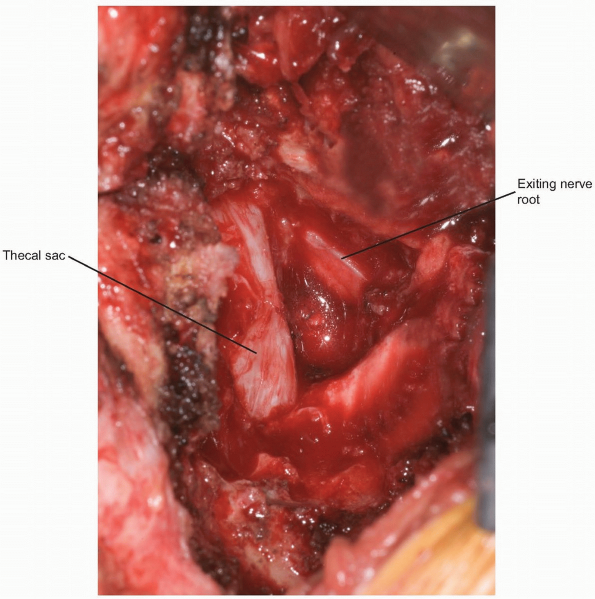

A rongeur or high-speed burr is then used

portion of the inferior lamina (Fig. 14-21). This will allow release of the insertion of the ligamentum flavum from the superior lamina of the caudal vertebra (Fig. 14-22). Immediately underneath this ligament is the epidural fat, thecal sac, and exiting nerve roots (Fig. 14-23).

After sufficient bone and ligamentum flavum have been removed the exiting nerve root should be visualized (Fig. 14-23).